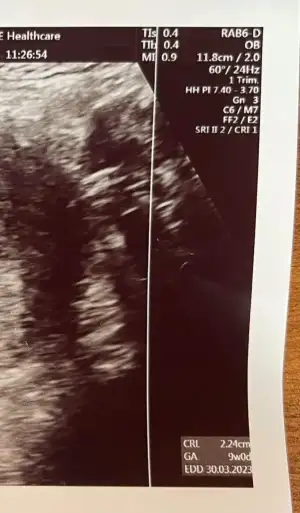

crl 2,24 cm yazıyor 9weeks 0 day ibaresi var :KK36:

hatta fetale karar verirsem tam ilk olurum, birazdan sana ultrasonu atıcam sıkıysa yorumla bayan cinsiyettahmincimiz

ekliyorum yandaki yazıları bi bakar mısın :KK22:

• uly.webp

uly.webp

32,7 KB · Görüntüleme: 87